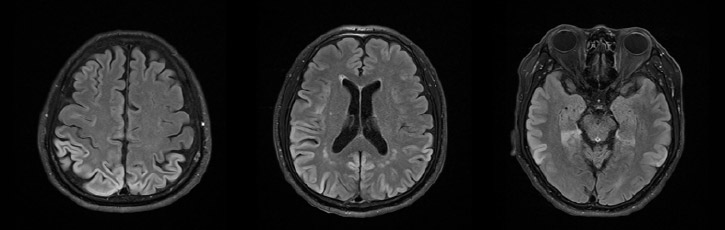

입원 후 시행한 뇌자기공명영상에서는 FLAIR에서 측두엽과 두정엽에서 대뇌 겉질의 고 신호 강도를

보이는 병변이 관찰되었으나 기저핵에서는 병변이 관찰되지 않았다. FP-CIT PET 영상에서는 정상 소견을

보였다. 또한 뇌파 검사 상에서는 양측 전두엽에서 세타 파와 델타 파가 관찰되었으나 주기적 극파는

관찰되지 않았다. 추가적으로 시행한 K-MMSE에서 22점이 확인되어 이전에 비하여 저하된 소견을

보였다.